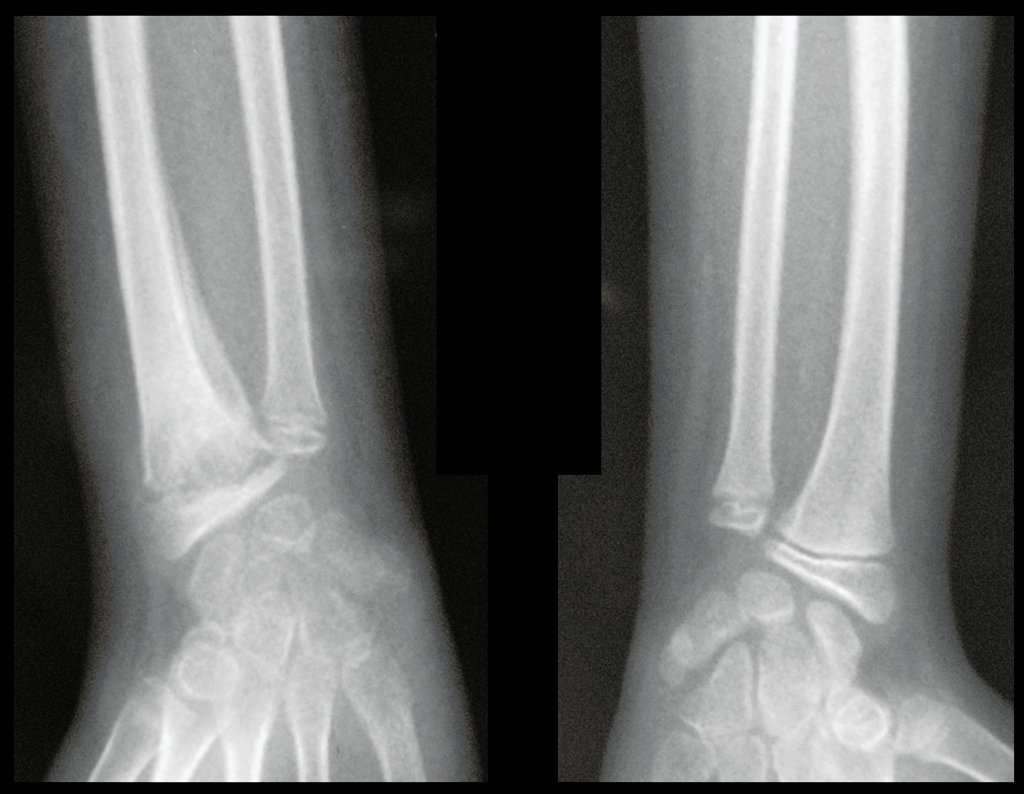

A los once años sufrió un traumatismo en la mano derecha en abril de 2015, siendo diagnosticada una fractura, la cual fue tratada con inmovilización durante 14 días, figuras 0a y 0b,

Después de una semana, el 14/08/2015, se retiró la férula y se encontró edema residual en la muñeca y dolor local. La semana siguiente, el 17/08/2015, fue evaluado por otro ortopedista quien repitió las radiografías y diagnosticó un quiste en el radio y una pequeña fractura arriba, figuras 1 a 5.